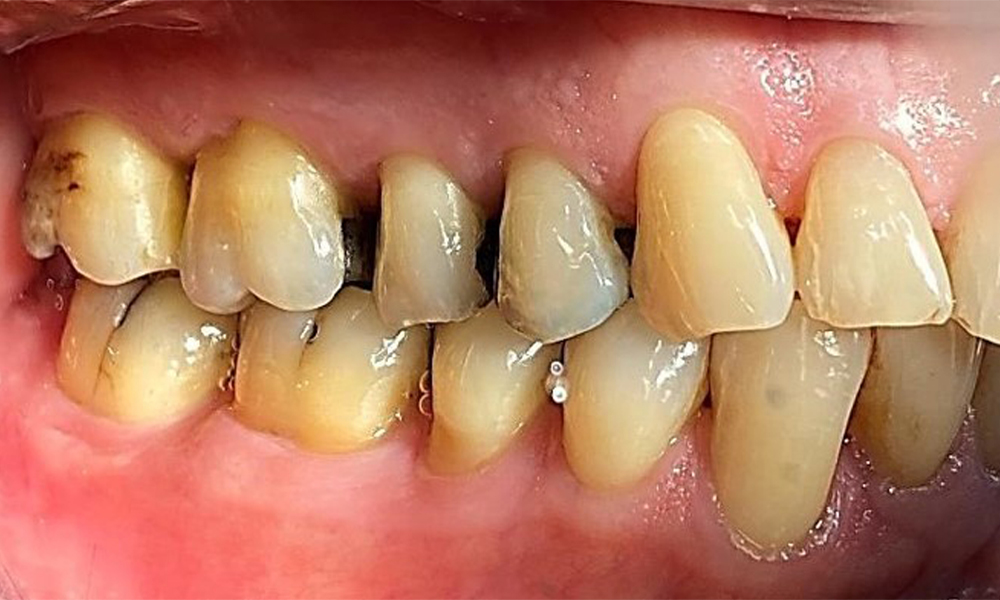

Десен страничен изглед. Загуба на интерденталните папили.

Фиг. 3 Десен страничен изглед. Загуба на интерденталните папили. © д-р Р. Крапф

Пациентът има пълно съзъбие с 28 зъба, което включва амалгамни и композитни пломби в областта на моларите и премоларите. На зъб 14 има видима клинична маргинална празнина. Зъб 27 има адекватна златна инкрустация. Налице са и генерализирани атриции и абразии. (фиг. 2, фиг. 3, фиг. 4, фиг. 5, фиг. 6)

Пациентът е с пародонтит II стадий, степен В (5). Клиничните дълбочини на сондиране от 1 до 3 mm са във физиологичния диапазон. Локализирани дълбочини на сондиране от 5 mm са наблюдавани медиопалатинално на 17 и 27. Налице са генерализирани рецесии от 1 до 3 mm с частична загуба на интердентални папили (фиг. 2, фиг. 3, фиг. 4)